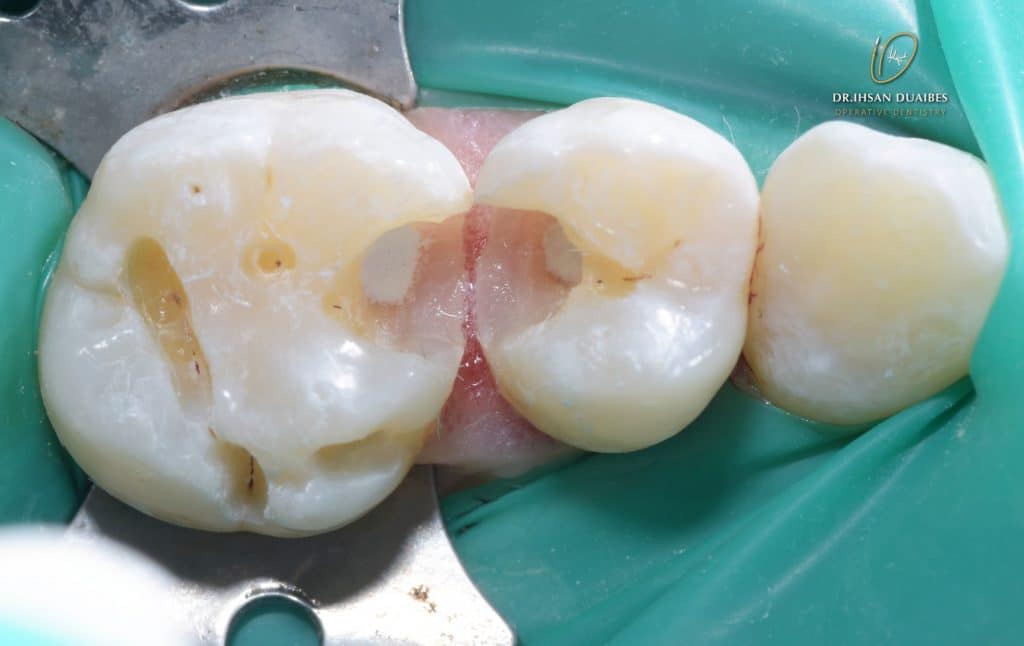

Pulp exposure ( is not bleeding )

Direct pulp caping with MTA ( Map one system facilitate the application ,then bond brush )

Now , put the gic and then finish the appointment, after the initial observation (to make sure that there are no symptoms) reduce the gic to make a permanent restoration using composite